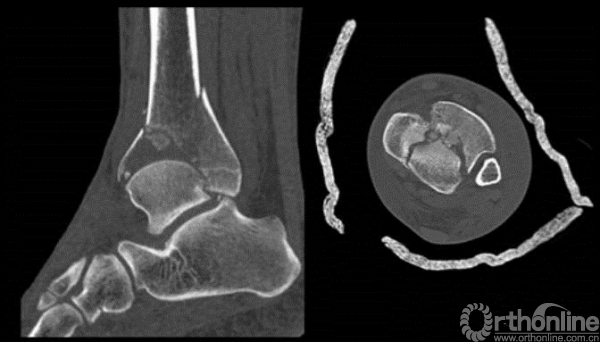

对于以下的骨折你怎么选择入路?

这样的骨折呢?

cole在2013年jot发表的文章描述了pilon骨折的骨折线图根据多例病例汇总到一起,颜色越深则越骨折线经过的可能性越大。

他将pilon骨折大致的骨块进行了分类,分别为后、前内、前外三个骨折块。

Pilon骨折的入路一共有5个,前内、前正中、前外、后内、后外。